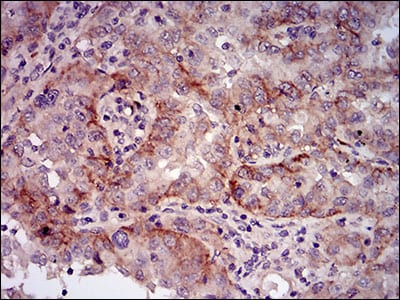

分类: 科研抗体货号: 30599别名: CDA02; EIF-2A; MST089; MSTP004; MSTP089应用: WB,IHC,FCM反应种属: Human,Mouse,Monkey,Rat

分类: 科研抗体货号: 30612别名: ATV; NBS; P95; NBS1; AT-V1; AT-V2应用: WB,IHC,IF,FCM反应种属: Human,Rat

分类: 科研抗体货号: 30611别名: NT; eN; NT5; NTE; eNT; CD73; E5NT; CALJA应用: WB,IHC反应种属: Human